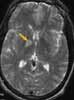

An MRI scan of the brain is ordered to determinethe cause of the patient's continued left-sided weakness(Figure 1). The scan shows multiple small lesions of uncertainorigin within the right parietal lobe, basal ganglia,and temporal lobe. The scan also reveals a focal area ofcerebritis or a small parenchymal contusion with minimalincreased signal within the right basal ganglia on the T1-weighted image, which suggests petechial hemorrhage.

What does the unilateral location of the lesionssuggest-and how will you proceed to evaluate thisfinding?

The clustering of the lesions on the right side of thebrain suggests vascular emboli. Of note, the admittingphysician detected a significant heart murmur when sheexamined the patient in the quiet of his hospital room. Anechocardiogram is performed to evaluate the heart as apotential source of repeated embolization (Figure 2).